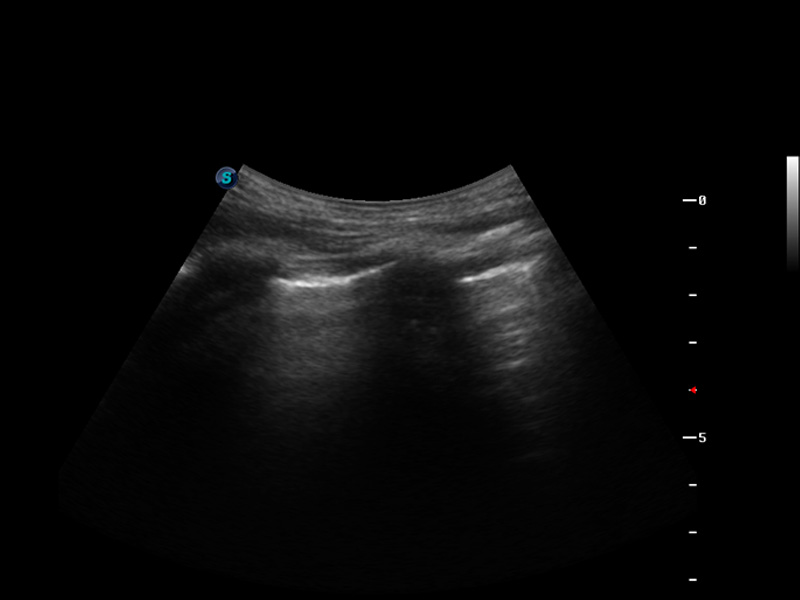

成像技术

脉冲反相谐波成像